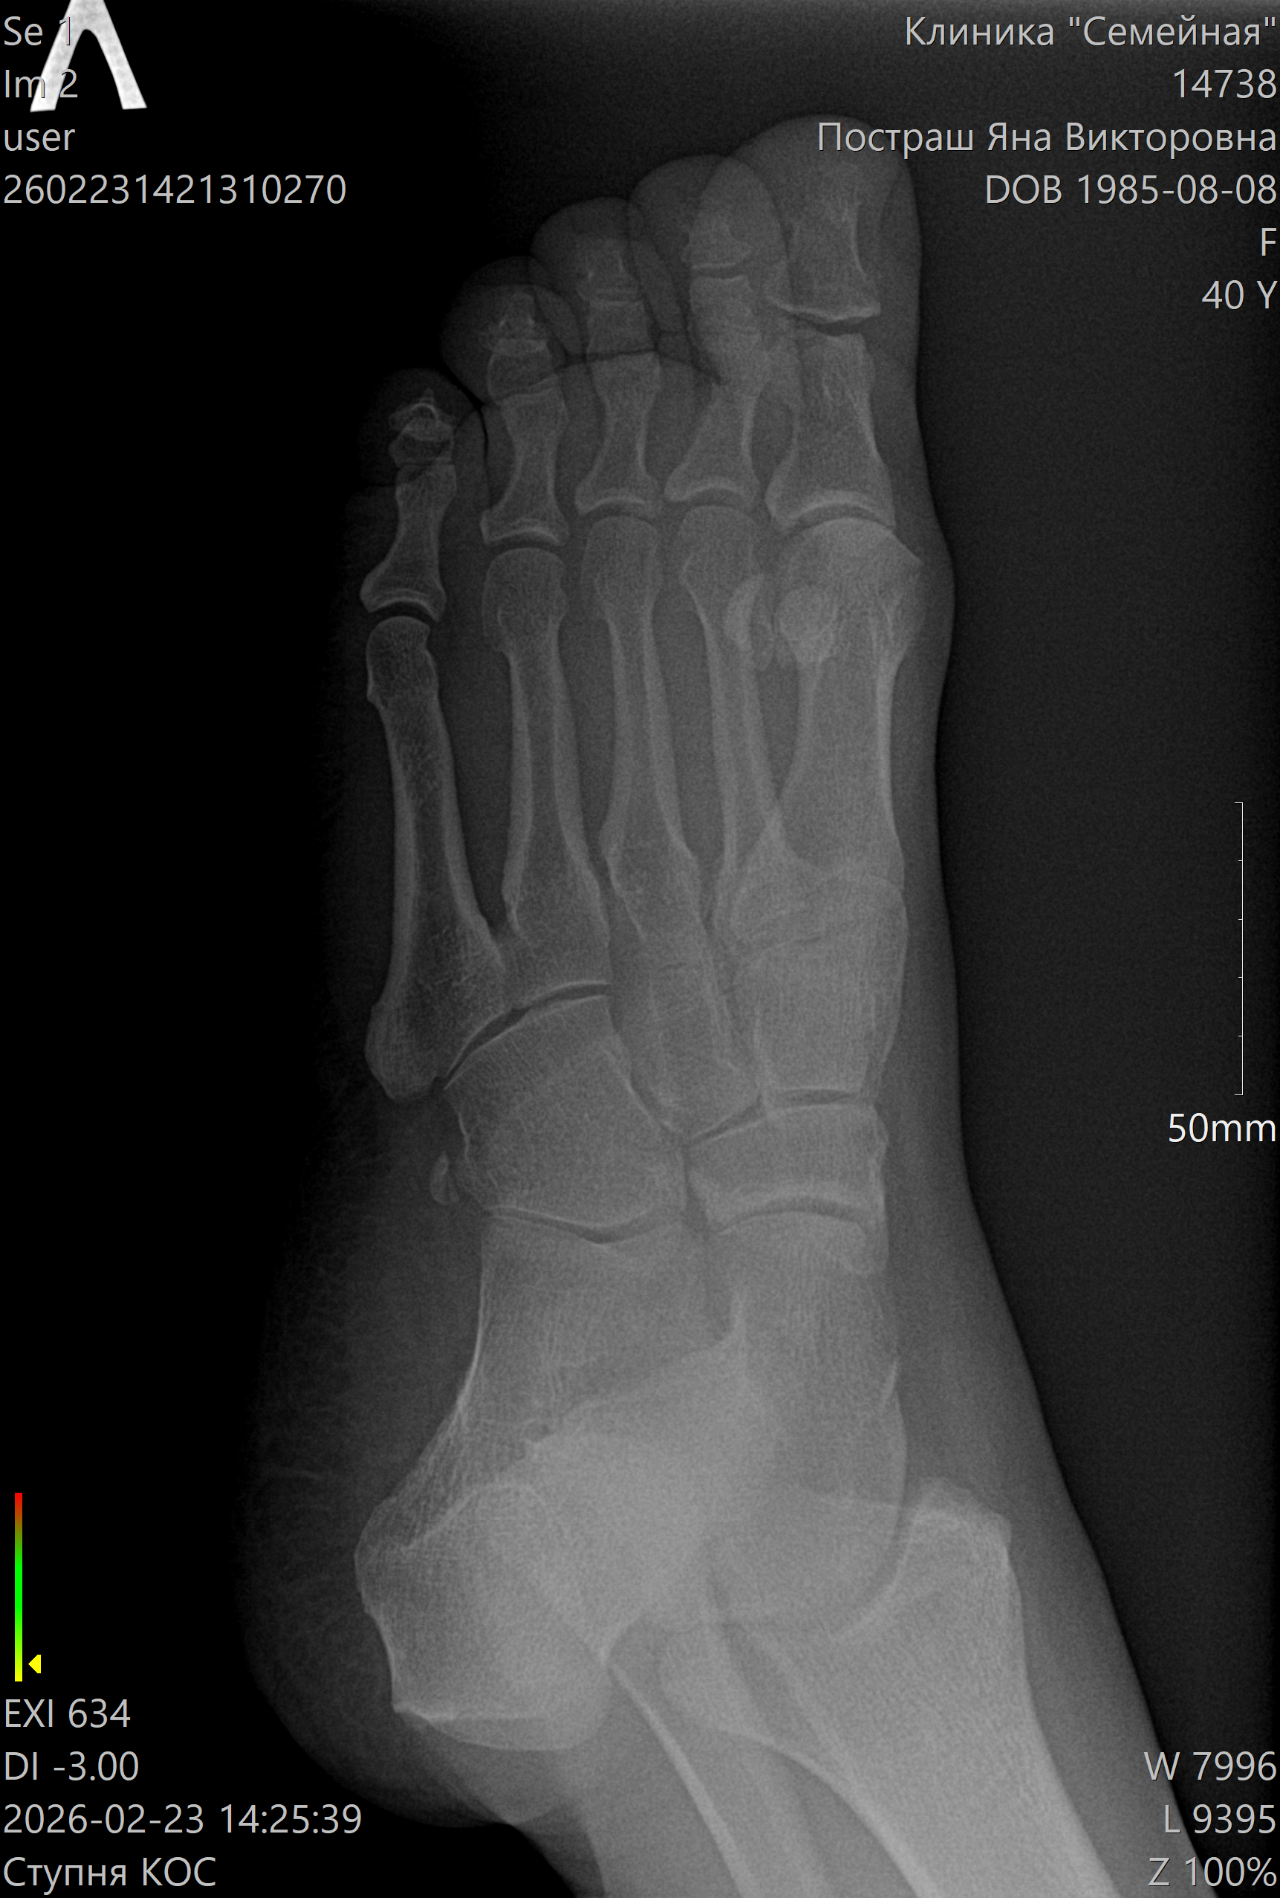

Краевой перелом дистальной фаланги

Несколько дней назад сильно ударила большой палец ноги. Поболело место ударно и все прошло бесследно. Спустя пару дней стала беспокоить боль в косточке при надавливании - сначала случайно задела, затем стала наблюдать. Боль не сильная, периодическая. Сделала рентген. К травматологу собираюсь на прием, но записи нет на ближайшее время. Внешне нога выглядит как обычно. Нет отека, синяка, подвижность не нарушена.

Какая моя тактика для заживления перелома?